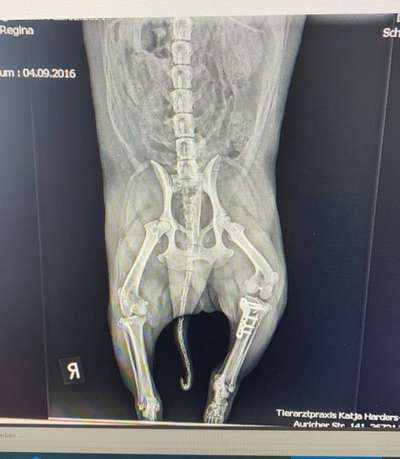

Hallo zusammen, Mein Hund Bobby 4,5Jahre alt hatte im Januar 2021 ein Kreuzbandriss linke Seite siehe da im März war die rechte Seite auch gerissen beide Beine haben wir in der Tierklinik Dr. Berger in Heede mit der TPLO versorgen lassen. Ich wollte nur mal fragen ob schon jemand Erfahrungen mit sowas gemacht hat und wie so die Heilungsdauer war können Sie sich irgendwann wieder ganz normal schmerzlos verhalten und wieder alles tun wie wandern, springen, rennen und toben? Würde mich sehr interessiert was Ihr für Erfahrungen gemacht habt.

Hallo, meine Maus, beide Beine im ersten Jahr... bei beiden Beinen wurde eine TPLO gemacht, letzte im September. Seit Dezember läuft wieder normal. Durch die Platten ist alles super stabil aber er musste durch die lange Pause (ca.8Wochen) erstmal mühselig wieder Kondition aufbauen. Er wollte aber schon nach 3Wochen wieder durchstarten.

Ja meiner kann das, hat jedoch zwei Platinimplantate bekommen, dass wichtigste ist jedoch das du auf sein Gewicht achtest und viel Physiotherapie machst, damit er im Hüftbereich und in den beiden hinterläufen viel Muskeln aufbaut, ansonsten kommt es zu weiteren Hüftschäden